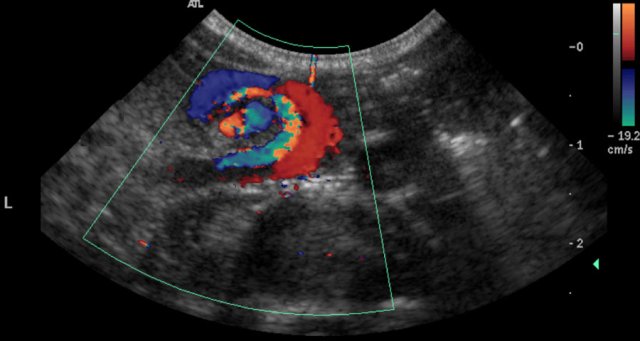

Here ultrasound images of a neonate who presented with an acute abdomen.

An ultrasound antenatally had detected a duplication cyst.

On the ultrasound there is a whirlpool sign of the vessels.

Torsion of the cyst and the mesentery had resulted in a volvulus.

This is a medical emergency and consequently the neonate went straight to the operating room.